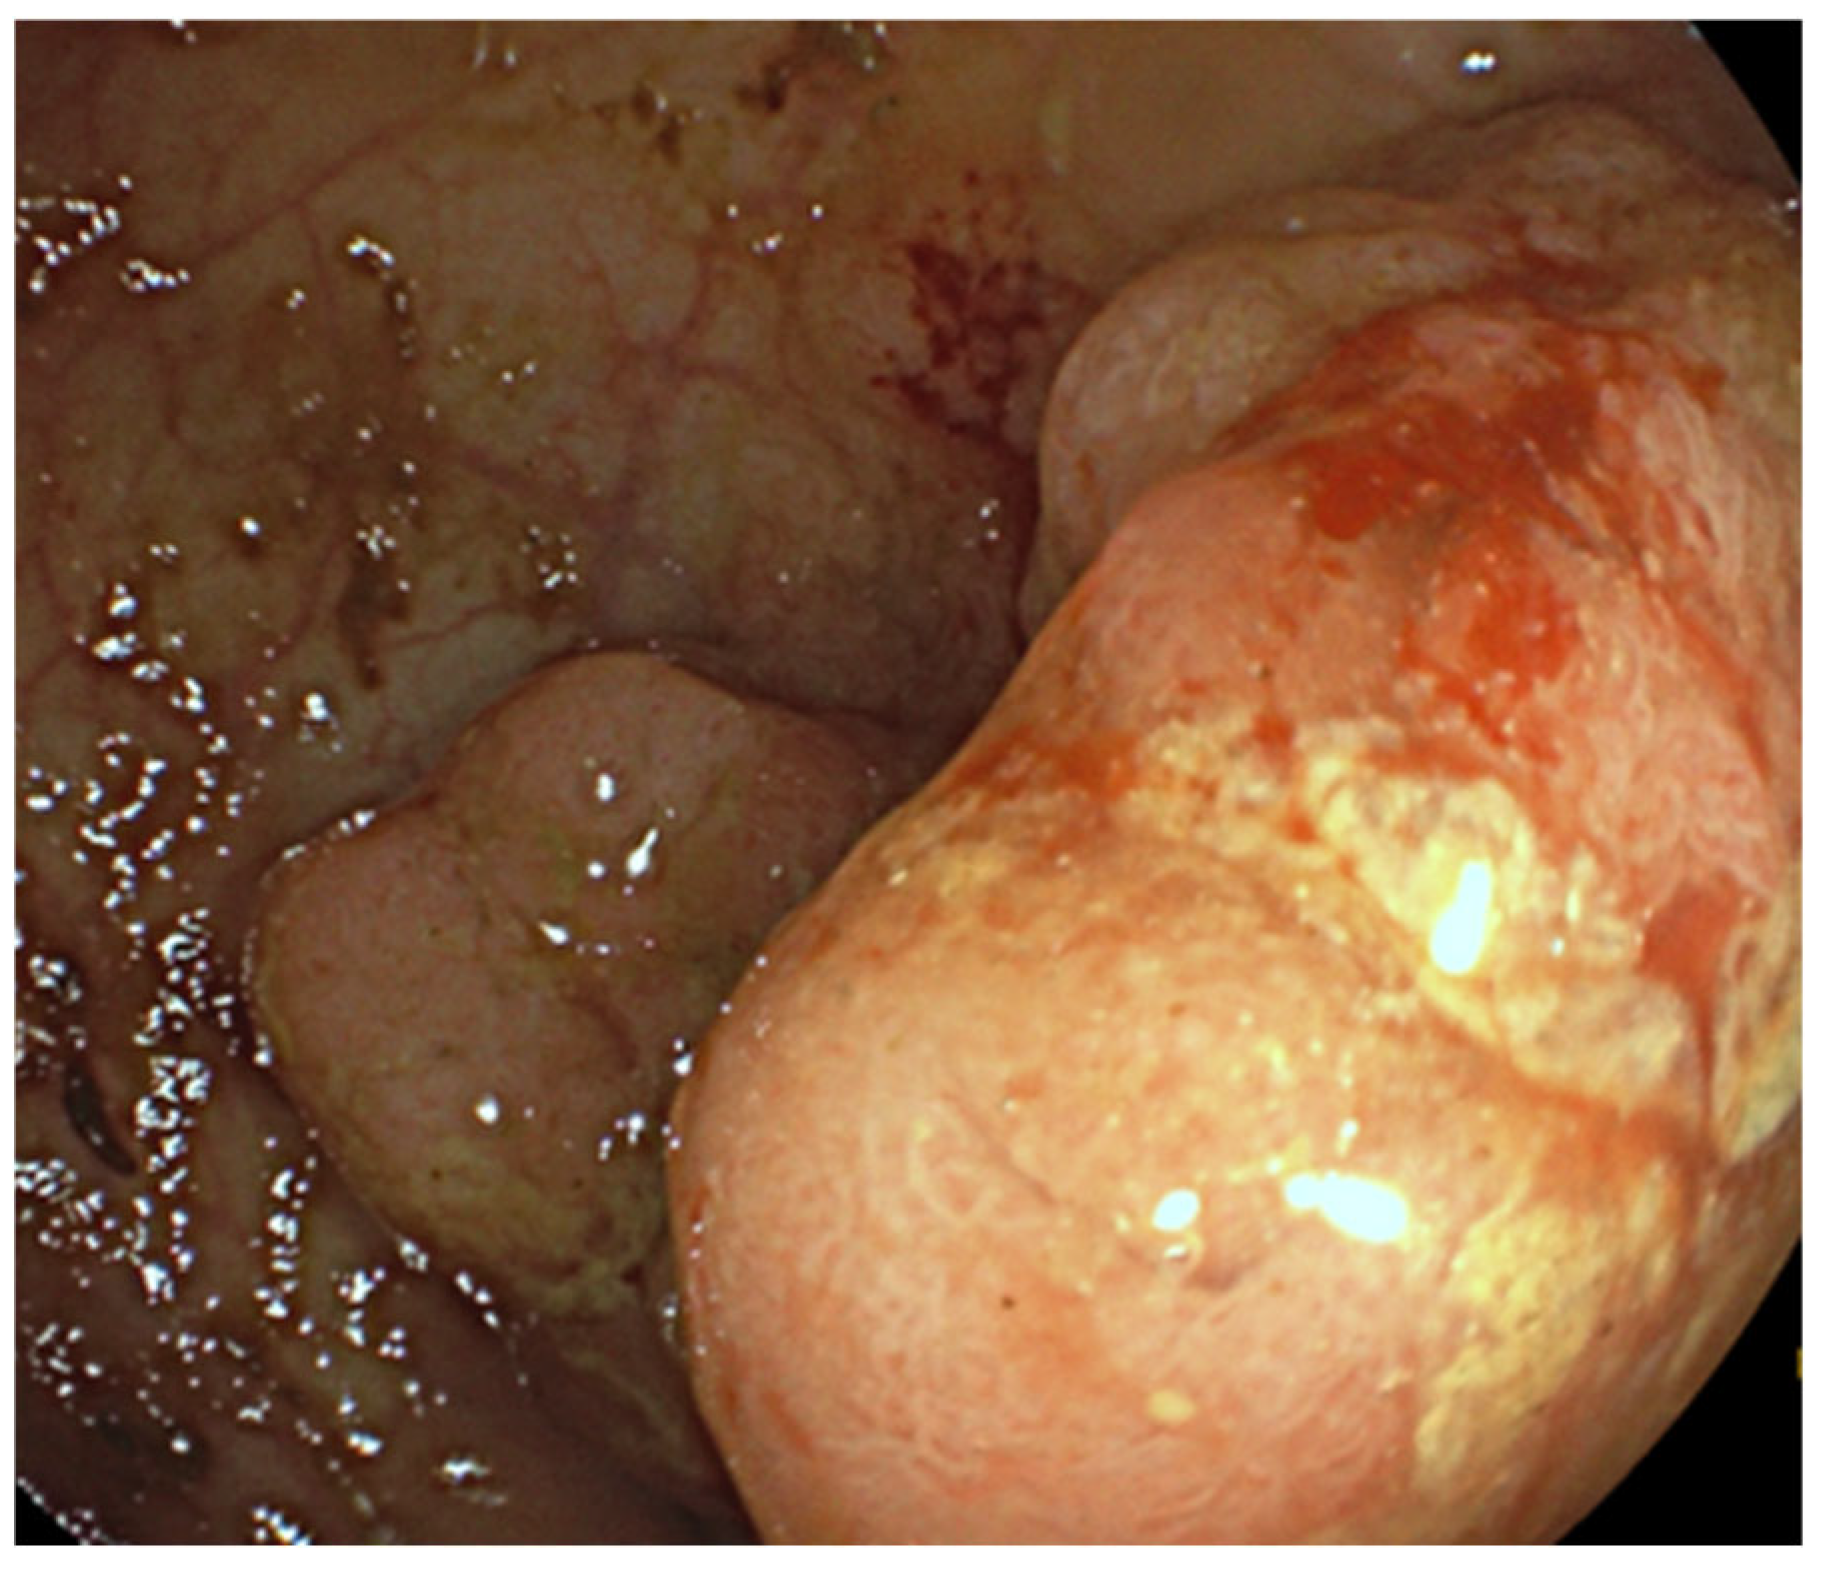

2.1. Case Presentation and Clinical Follow-Up